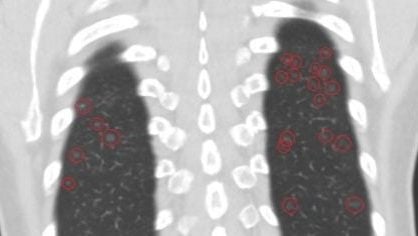

六旬妇肺变“满天星”毛玻璃 医生:工作环境导致!

台湾一名60岁妇人日前前往医院检查,胸腔电脑断层图意外发现肺部布满数十颗“毛玻璃状”结节,医师形容如“满天星”般密布。经详细问诊后,发现该妇人长年从事制鞋业,长期暴露在含甲苯(Toluene)等有机溶剂环境中,且每逢上班就会出现咳嗽、胸闷等不适症状。